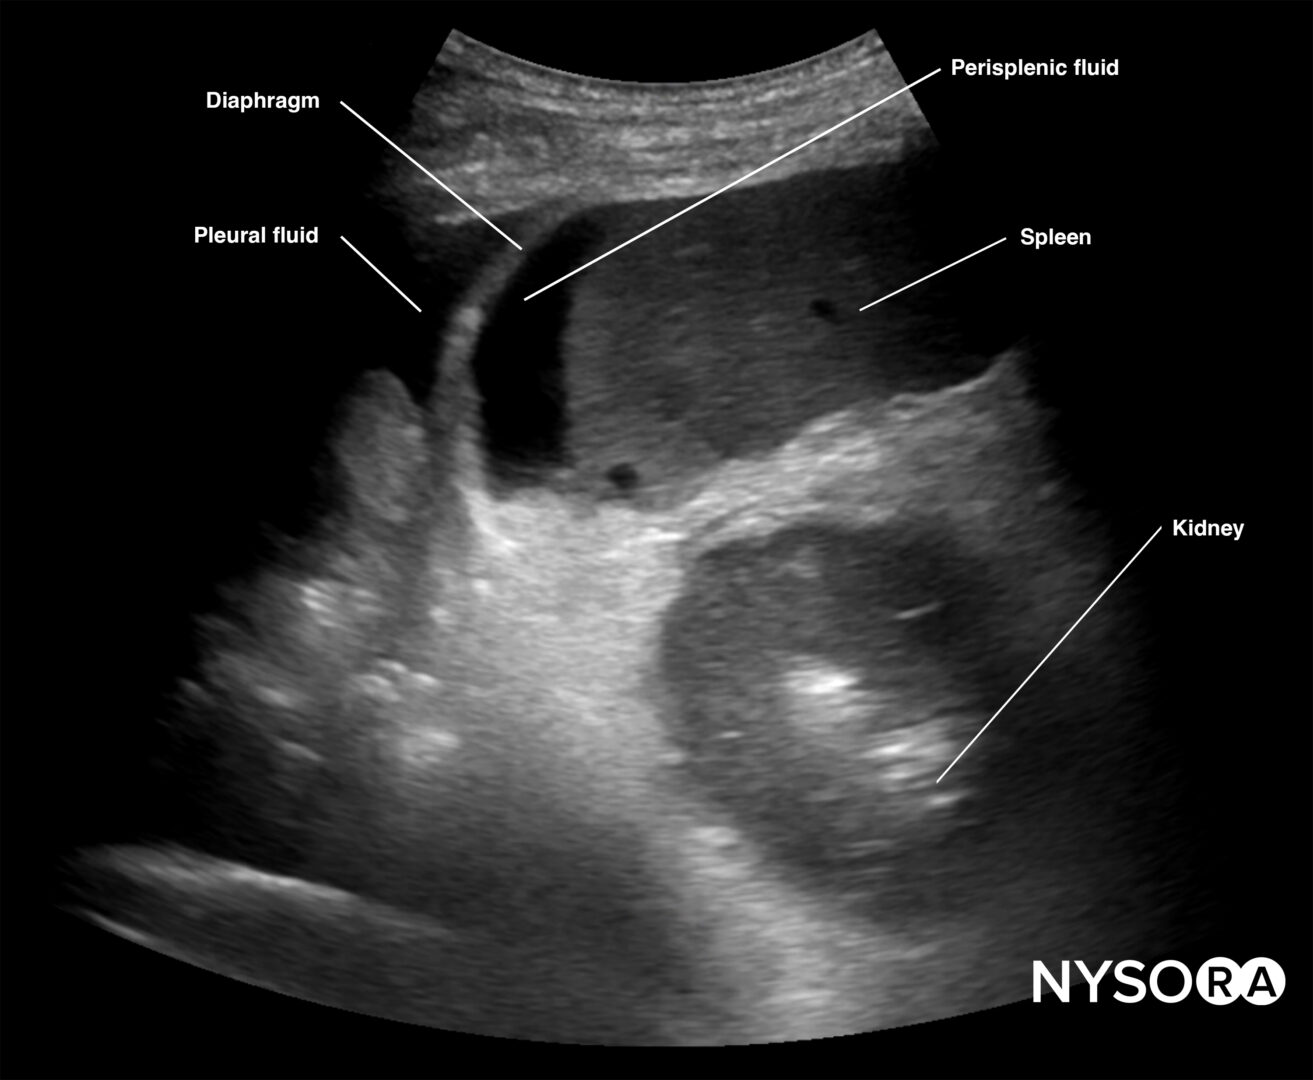

Intraperitoneal fluid often collects between the spleen and the diaphragm (perisplenic space). Fluid may also accumulate in other locations, such as the splenorenal recess. If intrathoracic free fluid is present, it can be identified above the diaphragm.

Free intraperitoneal fluid can be located in the perisplenic space.

Always assess the area above the diaphragm for free fluid in the RUQ and LUQ.

Free fluid or pleural effusion above the diaphragm.